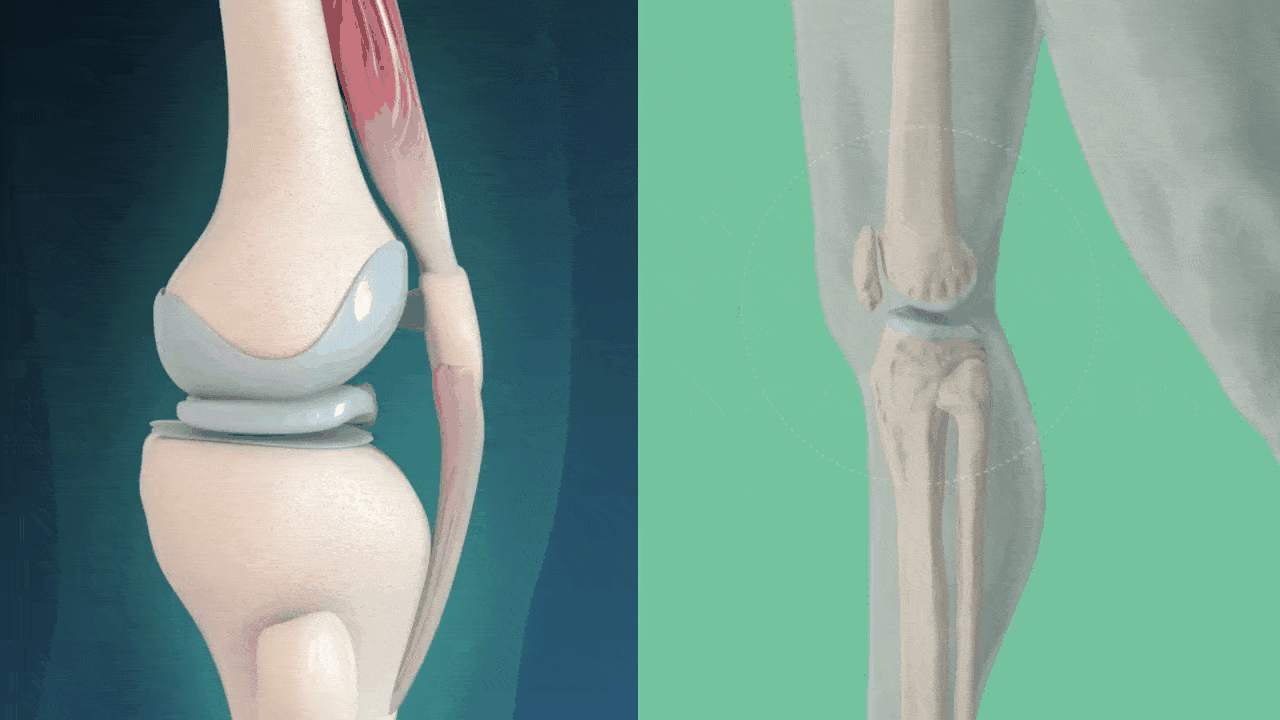

What if I told you that the pain and stiffness you feel are caused by the wear and tear of your cartilage, leading to uncomfortable friction?

Our knees are crucial for our mobility, and they bear the brunt of our body weight every day. They act as shock absorbers, cushioning the impact from walking, running, and other daily activities.

As the cartilage wears away over time, the bones start to rub against each other, causing intense pain and discomfort. This friction leads to discomfort, swelling, and a significant reduction in mobility.

However, the truth of the matter is that the root cause is often accumulated pressure and stress that has been building up on our knee joints every single day.

Years of repetitive movements, poor posture, and lack of proper care weaken the cartilage, setting the stage for injuries to happen more easily.

Similarly, constant use and strain without adequate support and recovery lead to the deterioration of knee cartilage.